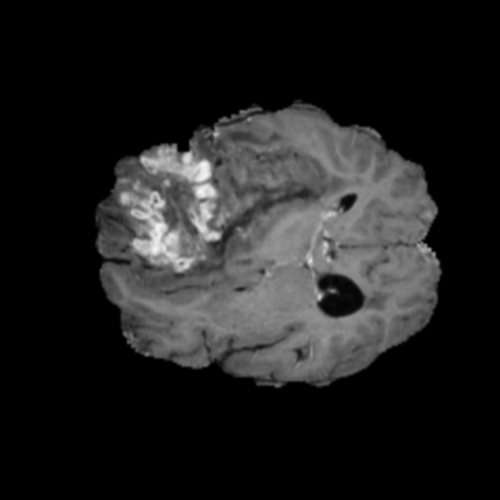

Ejemplos de Modalidades MRI

Visualización de las 4 modalidades de resonancia magnética y las segmentaciones de zonas tumorales utilizadas para entrenar el modelo

Glioma de Alto Grado (HGG)

FLAIR HGG

FLAIR

T1ce HGG

T1ce

T2 HGG

T2

T1 HGG

T1

Núcleo HGG

Núcleo

Edema HGG

Edema

Realce HGG

Realce

Tumor Completo HGG

Tumor Completo

Núcleo Edema Realce